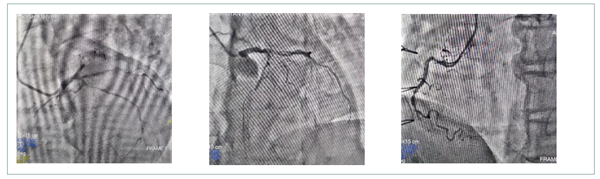

另一位袁先生的冠状动脉造影显示原位血管左前降支闭塞,左回旋支80%以上狭窄,右冠状动脉远段闭塞,LIMA桥血管通畅,右冠桥血管中段狭窄,回旋支静脉桥血管开口及中段已经出现90%以上狭窄。原位血管病变时间很长,且受到桥血管血流影响,开通可能性非常低,刘巍主任决定对桥血管进行介入治疗。

原位血管可见弥漫性狭窄合并慢性闭塞病变

术中显示,袁先生SVG-LCX中段斑块负荷非常重。刘巍主任首先尝试了远端保护装置送至桥血管远端,但由于血管迂曲,保护装置无法送至远端,所以准分子激光就成了最重要的治疗手段。